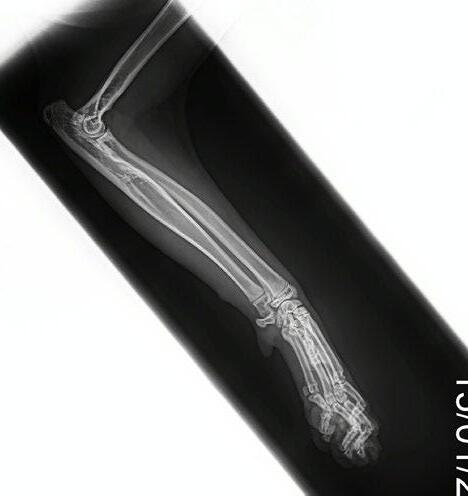

Four weeks later, Hotch was presented with marked lameness and a firm marked swelling of his left antebrachium. There were no obvious wounds or scabs, although he was hyperthermic. He was admitted for radiographs (see images) under sedation (dexmedetomidine 5µg/kg, methadone 0.3 mg/kg).

1

Radiographs showed signs of acute suppurative osteomyelitis, likely bacterial. This has a characteristic appearance in kittens, as the periosteum is not so strongly attached to the bone cortex, and the neutrophilic exudate lifts the periosteum, which then makes a florid new bone response ( blue arrow). Usually, these infections arise after a bite wound. The periosteal new bone formation is florid. Patchy portions of cortical bone lysis (yellow arrow) are also evident towards the centre of the lesion. At this stage we contacted Dr Richard Malik at the CVE as I had never seen anything like this before. Richard was also concerned about mild nutritional secondary hyperparathyroidism (NSH) due to the bone cortices appearing pale (osteopaenic), with an area of increased relative radiodensity immediately next to the growth plates (orange arrow). In NSH, the only normal bone is that laid down by endochondral ossification at the growth plates (and in this case—where new bone is laid down to wall off the infected bone), the rest of the skeleton is being broken down by osteoclasts under the direction of PTH.

Figure 1. Radiographs of the affected limb at presentation

2

3 4A 4B 4C

Note the generalised mild osteopaenia, with narrow lamellated cortices of many of the long bones.

Figure 3. Radiograph of the affected leg showing resolving infection and remodeling of the lesion back into a more normal skeletal appearance

Figure 4. Final radiographs showing near normal appearance of the lesion (A & B) after extensive remodelling during growth. C is the contralateral normal limb for purposes of comparison.